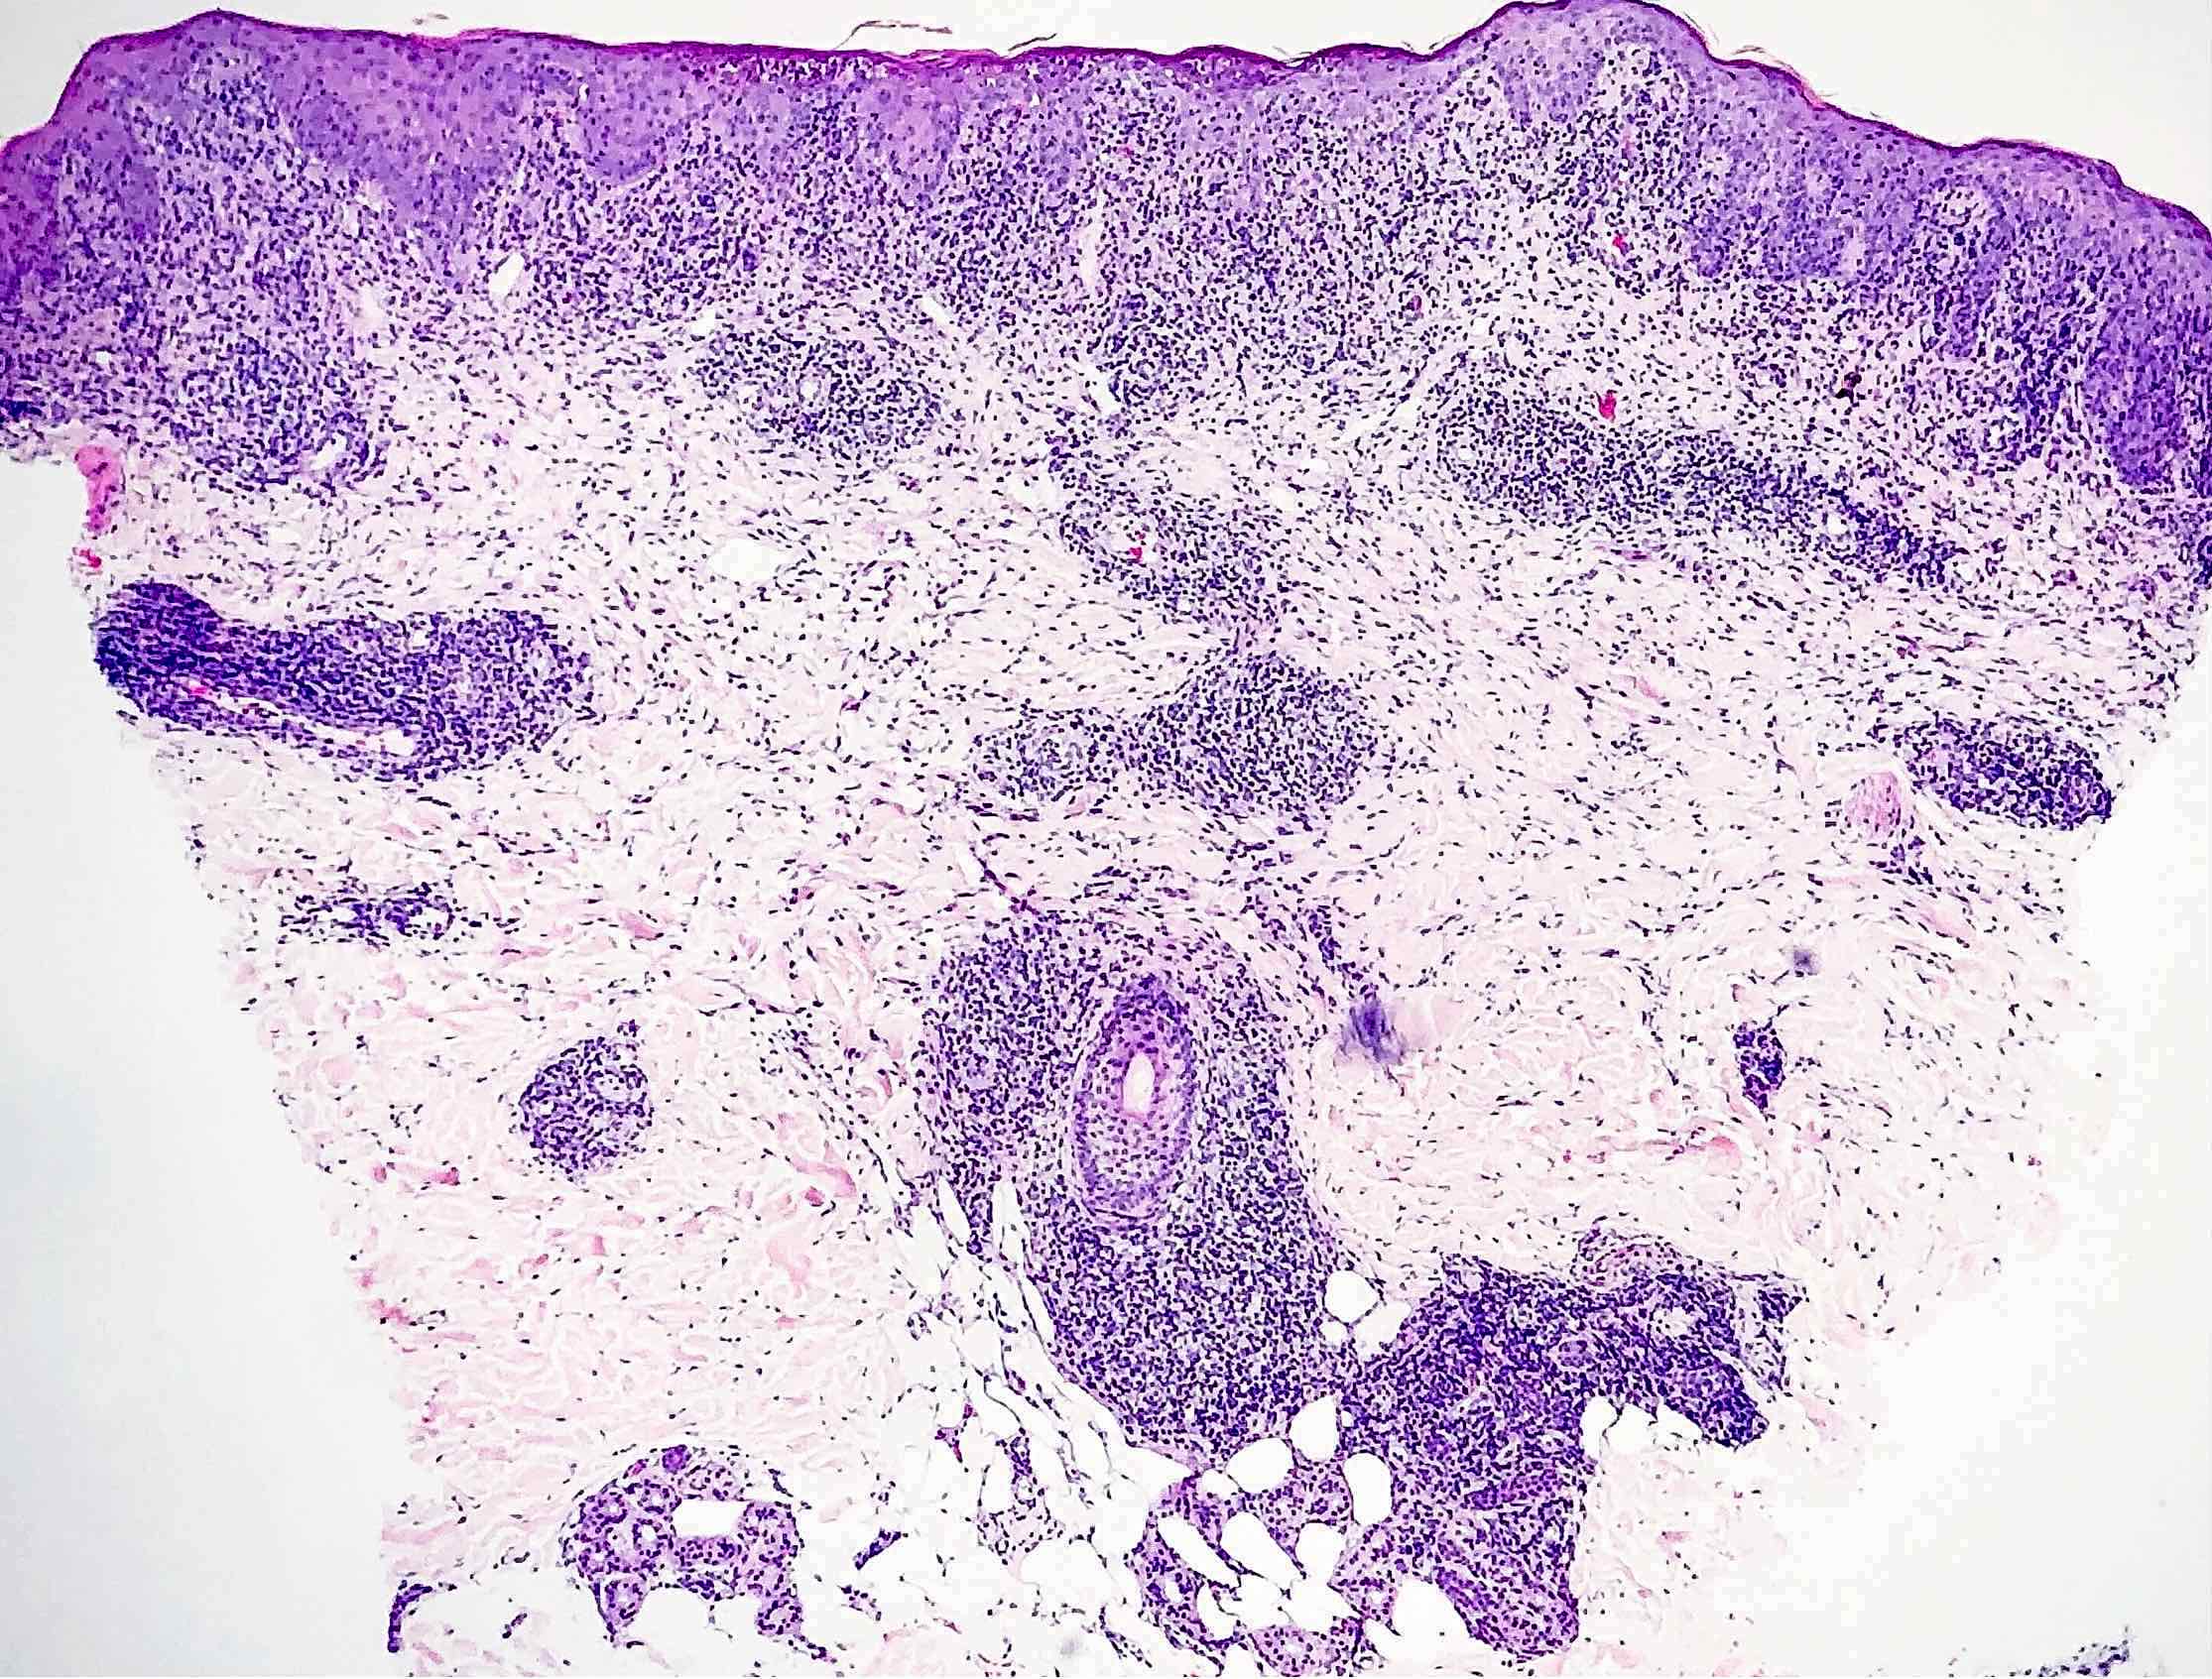

- Secondary syphilis:

- Lichenoid superficial and deep perivascular and periadnexal lymphohistiocytic inflammation with admixed plasma cells

- Plasma cells may be absent in 33% of biopsies

- Marked endothelial swelling and proliferation of blood vessels can be seen

- Commonly identified are vacuolar interface change, acanthosis or lymphocyte exocytosis

- In late secondary syphilis, granulomatous inflammation may be present

- Microabscess formation of the hair follicle has also been seen

- Condyloma lata (lesions on genital skin) show marked epidermal hyperplasia and inflammatory infiltrate akin to secondary syphilis